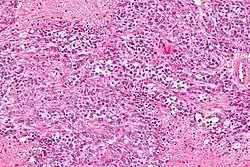

- Elevated 1,25(OH)2D (see calcitriol under Vitamin D) levels (e.g., sarcoidosis and other granulomatous diseases such as tuberculosis, berylliosis, histoplasmosis, Crohn's disease, and granulomatosis with polyangiitis)